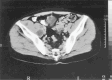

Musculoskeletal tuberculosis (TB) accounts for approximately 10% of all extrapulmonary TB cases in the United States and is the third most common site of extrapulmonary TB after pleural and lymphatic disease. Vertebral involvement (tuberculous spondylitis, or Pott's disease) is the most common type of skeletal TB, accounting for about half of all cases of musculoskeletal TB. The presentation of musculoskeletal TB may be insidious over a long period and the diagnosis may be elusive and delayed, as TB may not be the initial consideration in the differential diagnosis. Concomitant pulmonary involvement may not be present, thus confusing the diagnosis even further. Early diagnosis of bone and joint disease is important to minimize the risk of deformity and enhance outcome. The introduction of newer imaging modalities, including MRI (imaging procedure of choice) and CT, has enhanced the diagnostic evaluation of patients with musculoskeletal TB and for directed biopsies of affected areas of the musculoskeletal system. Obtaining appropriate specimens for culture and other diagnostic tests is essential to establish a definitive diagnosis and recover M. tuberculosis for susceptibility testing. A total of 6 to 9 months of a rifampin-based regimen, like treatment of pulmonary TB, is recommended for the treatment of drug susceptible musculoskeletal disease. Randomized trials of tuberculous spondylitis have demonstrated that such regimens are efficacious. These data and those from the treatment of pulmonary TB have been extrapolated to form the basis of treatment regimen recommendations for other forms of musculoskeletal TB.